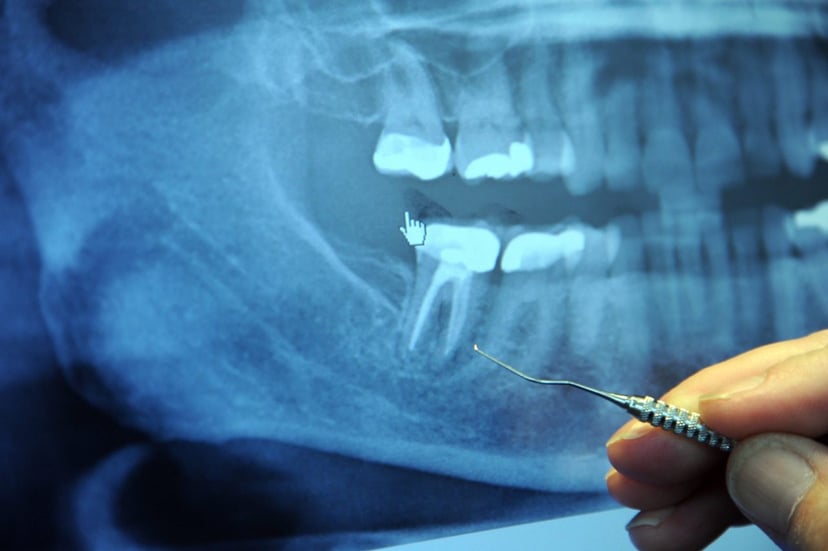

– Chụp X quang răng: Có thể thấy hình ảnh mờ vùng cuống, ranh giới không rõ ràng và dãn rộng dây chằng quanh cuống.

Chup X-quang có thể thấy rõ ổ viêm tại cuống răng

– Chụp X quang có thể thấy rõ ràng hình ảnh ổ mủ.